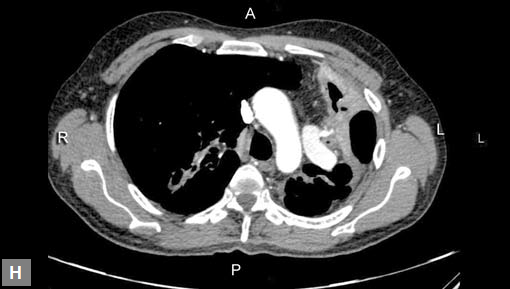

Figs 19A to Y (A to C) Scannogram (A), plain (B) and contrast study (C) show partial anomalous pulmonary venous connection; (D to F) Heterotaxy; (G) Aortic occlusion; (H and I) Aortic stents; (J) Aortic dissection with ‘Benz’ sign due to second dissection within the true lumen; (K, L and M) Aortic dissection with thrombus in pseudolumen following catheter angiogram; (N) Aortic dissection involving common carotid arteries and subclavian artery; (O, P, Q and R) Aortic dissection with right renal artery arising from true lumen and left renal artery from false lumen; (S, T, U and V) Stanford B dissection with extension Y to iliac vessels; (W to Y) Aneurysmal dilation of ascending aorta